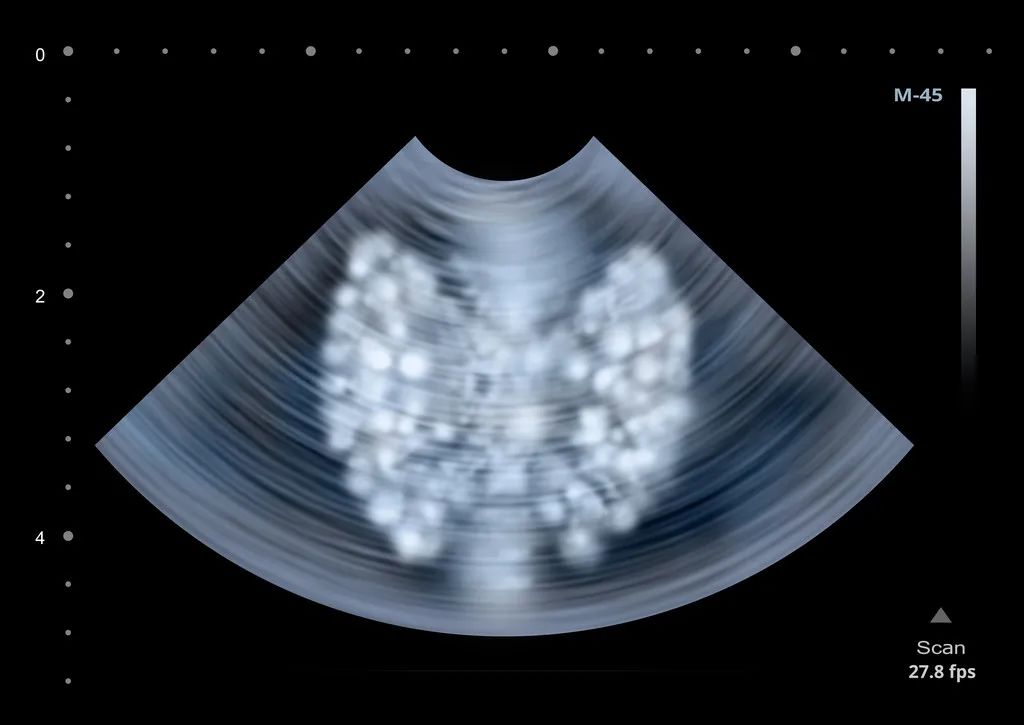

甲状腺位于“喉结”下方2~3厘米处,形似蝴蝶,是人体最大的内分泌器官。